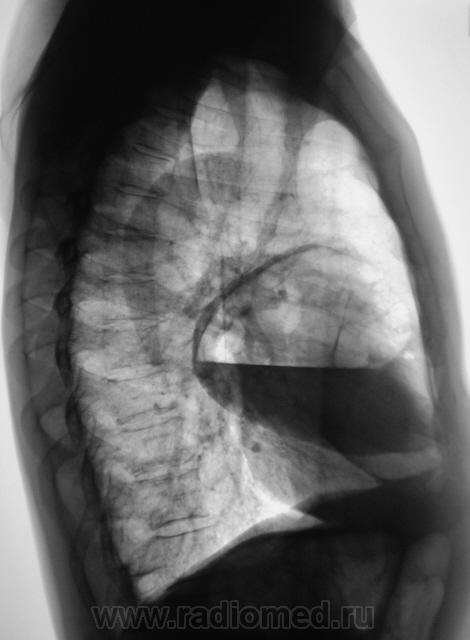

Произвели рентгенографию в стандартных проекциях.

Флюорограмма 2009 года.

сильно похоже на нагноившуюся кисту...

Она и есть.

Но, пациент жалоб не предъявляет...

Киста, точно киста. Был пациент на консультации у торакальщиков, будут готовить к плановой операции.

Но неужели содержимое гной?

Насчет содержимого знать не могу. Наша задача, на глубокой периферии. определить пациента "по профилю".